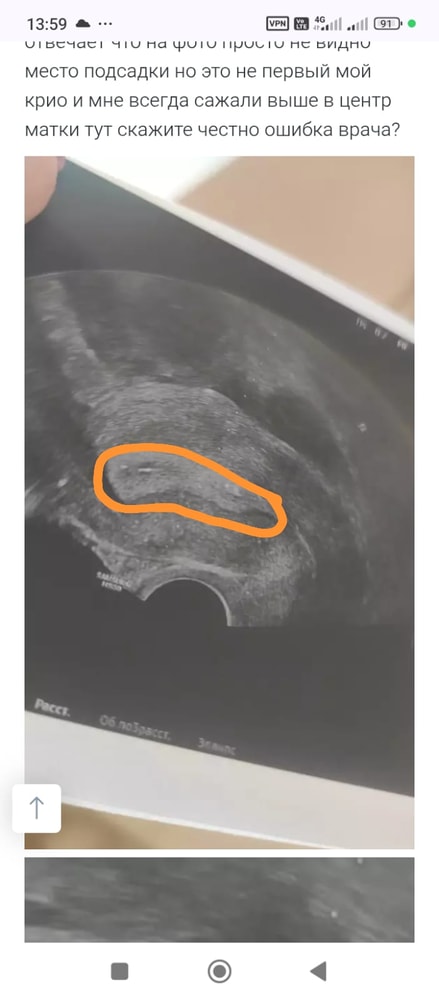

Дорогие девочки, смотрю на снимок после переноса и вижу что в отличие от первого раза где точечки на распечатанном УЗИ при подсадке были в середине матки сейчас они прям у самого низа матки где цервикальный канал

Могли бы вы посмотреть прислать фото куда вам подсадили эмбрион на вашем успешном крио? У кого были успехи с посадкой так низко? Я очень переживаю. Эмбрион после пгд и это просто немыслимо почему он так низко подсажен

напишите фамилию врача и куда вам подсадил. Я расстроилась очень. Доктор отвечает что на фото просто не видно место подсадки но это не первый мой крио и мне всегда сажали выше в центр матки тут скажите честно ошибка врача?